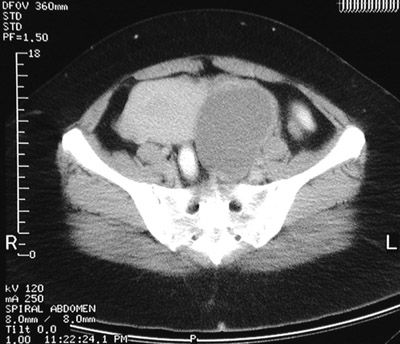

| These CT scan views of the pelvis demonstrate a uterus containing leiomyomata. The view above reveals a submucosal leiomyoma while the view below shows an intramural leiomyoma of the upper fundus. The fluid-filled structure on the left that is displacing the uterus to the left is an endometrioma of the ovary. |